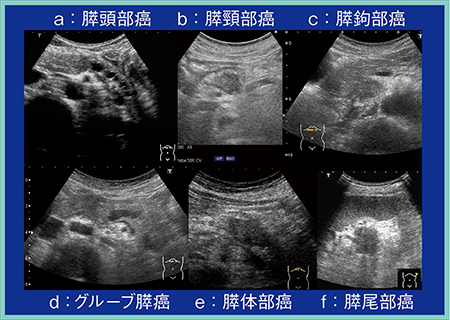

膵癌描出のポイントとして,発生部位,臨床症状,画像所見から膵臓を膵頭部,膵頸部,膵鉤部,グルーブ領域,膵体部,膵尾部の6領域に分けて考えると理解が深まる。

膵頭部は主膵管と総胆管の合流部で,ここに発生する癌は膵内胆管や主膵管の閉塞を伴い,十二指腸や上腸間膜動脈(SMA),上腸間膜静脈(SMV)に浸潤する。尾側の膵管が数珠状に拡張している様子が典型像として得られる(図2 a)。

膵頸部は膵頭部と膵体部の移行部で,門脈からSMVの腹側に位置しており,ここに発生する癌は膵外進展,腹腔動脈や総肝動脈への浸潤,主膵管への浸潤がある(図2 b)。胃の前庭部に浸潤しやすく,プローブを上に振り上げて観察することで,見逃し防止につながる。

膵鉤部はSMVの背側,SMVより左側に位置する。ここに発生する癌は膵外進展が強く,十二指腸水平脚やSMA,SMVに浸潤するほか,神経周囲浸潤も多い。また,後腹膜の深部に進展していくため,膵臓の腫瘍に気づきづらい。そのため,必ず十二指腸が見えなくなるところまでしっかりと観察することが重要である(図2 c)。

グルーブ領域は,十二指腸下行脚と膵頭部,総胆管に囲まれた溝(groove)を指し,ここに発生する癌は十二指腸や膵内胆管に浸潤する(図2 d)。グルーブ膵炎との鑑別診断も困難であり,十分注意して観察する必要がある。

このほか,膵体部に発生する癌(図2 e)は脾動脈,脾静脈に浸潤し,膵尾部に発生する癌(図2 f)は脾臓や脾門部に存在する消化管に浸潤するという特徴がある。

図2 膵癌発生部位・臨床症状・画像所見からの分類